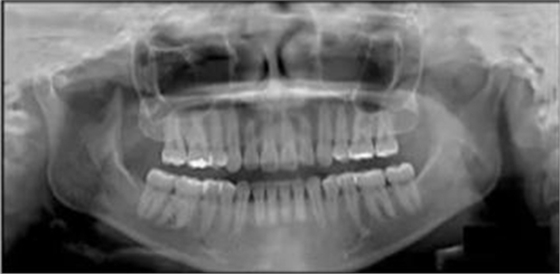

頭側(cè)分析提示為骨性安氏II類(ANB,8.4°;Wits,3.6mm),高角(SN-MP,44.9°),上頜切牙略舌傾(U1-SN,96.2°),下頜切牙略舌傾(IMPA,88。3°)(圖2;表)